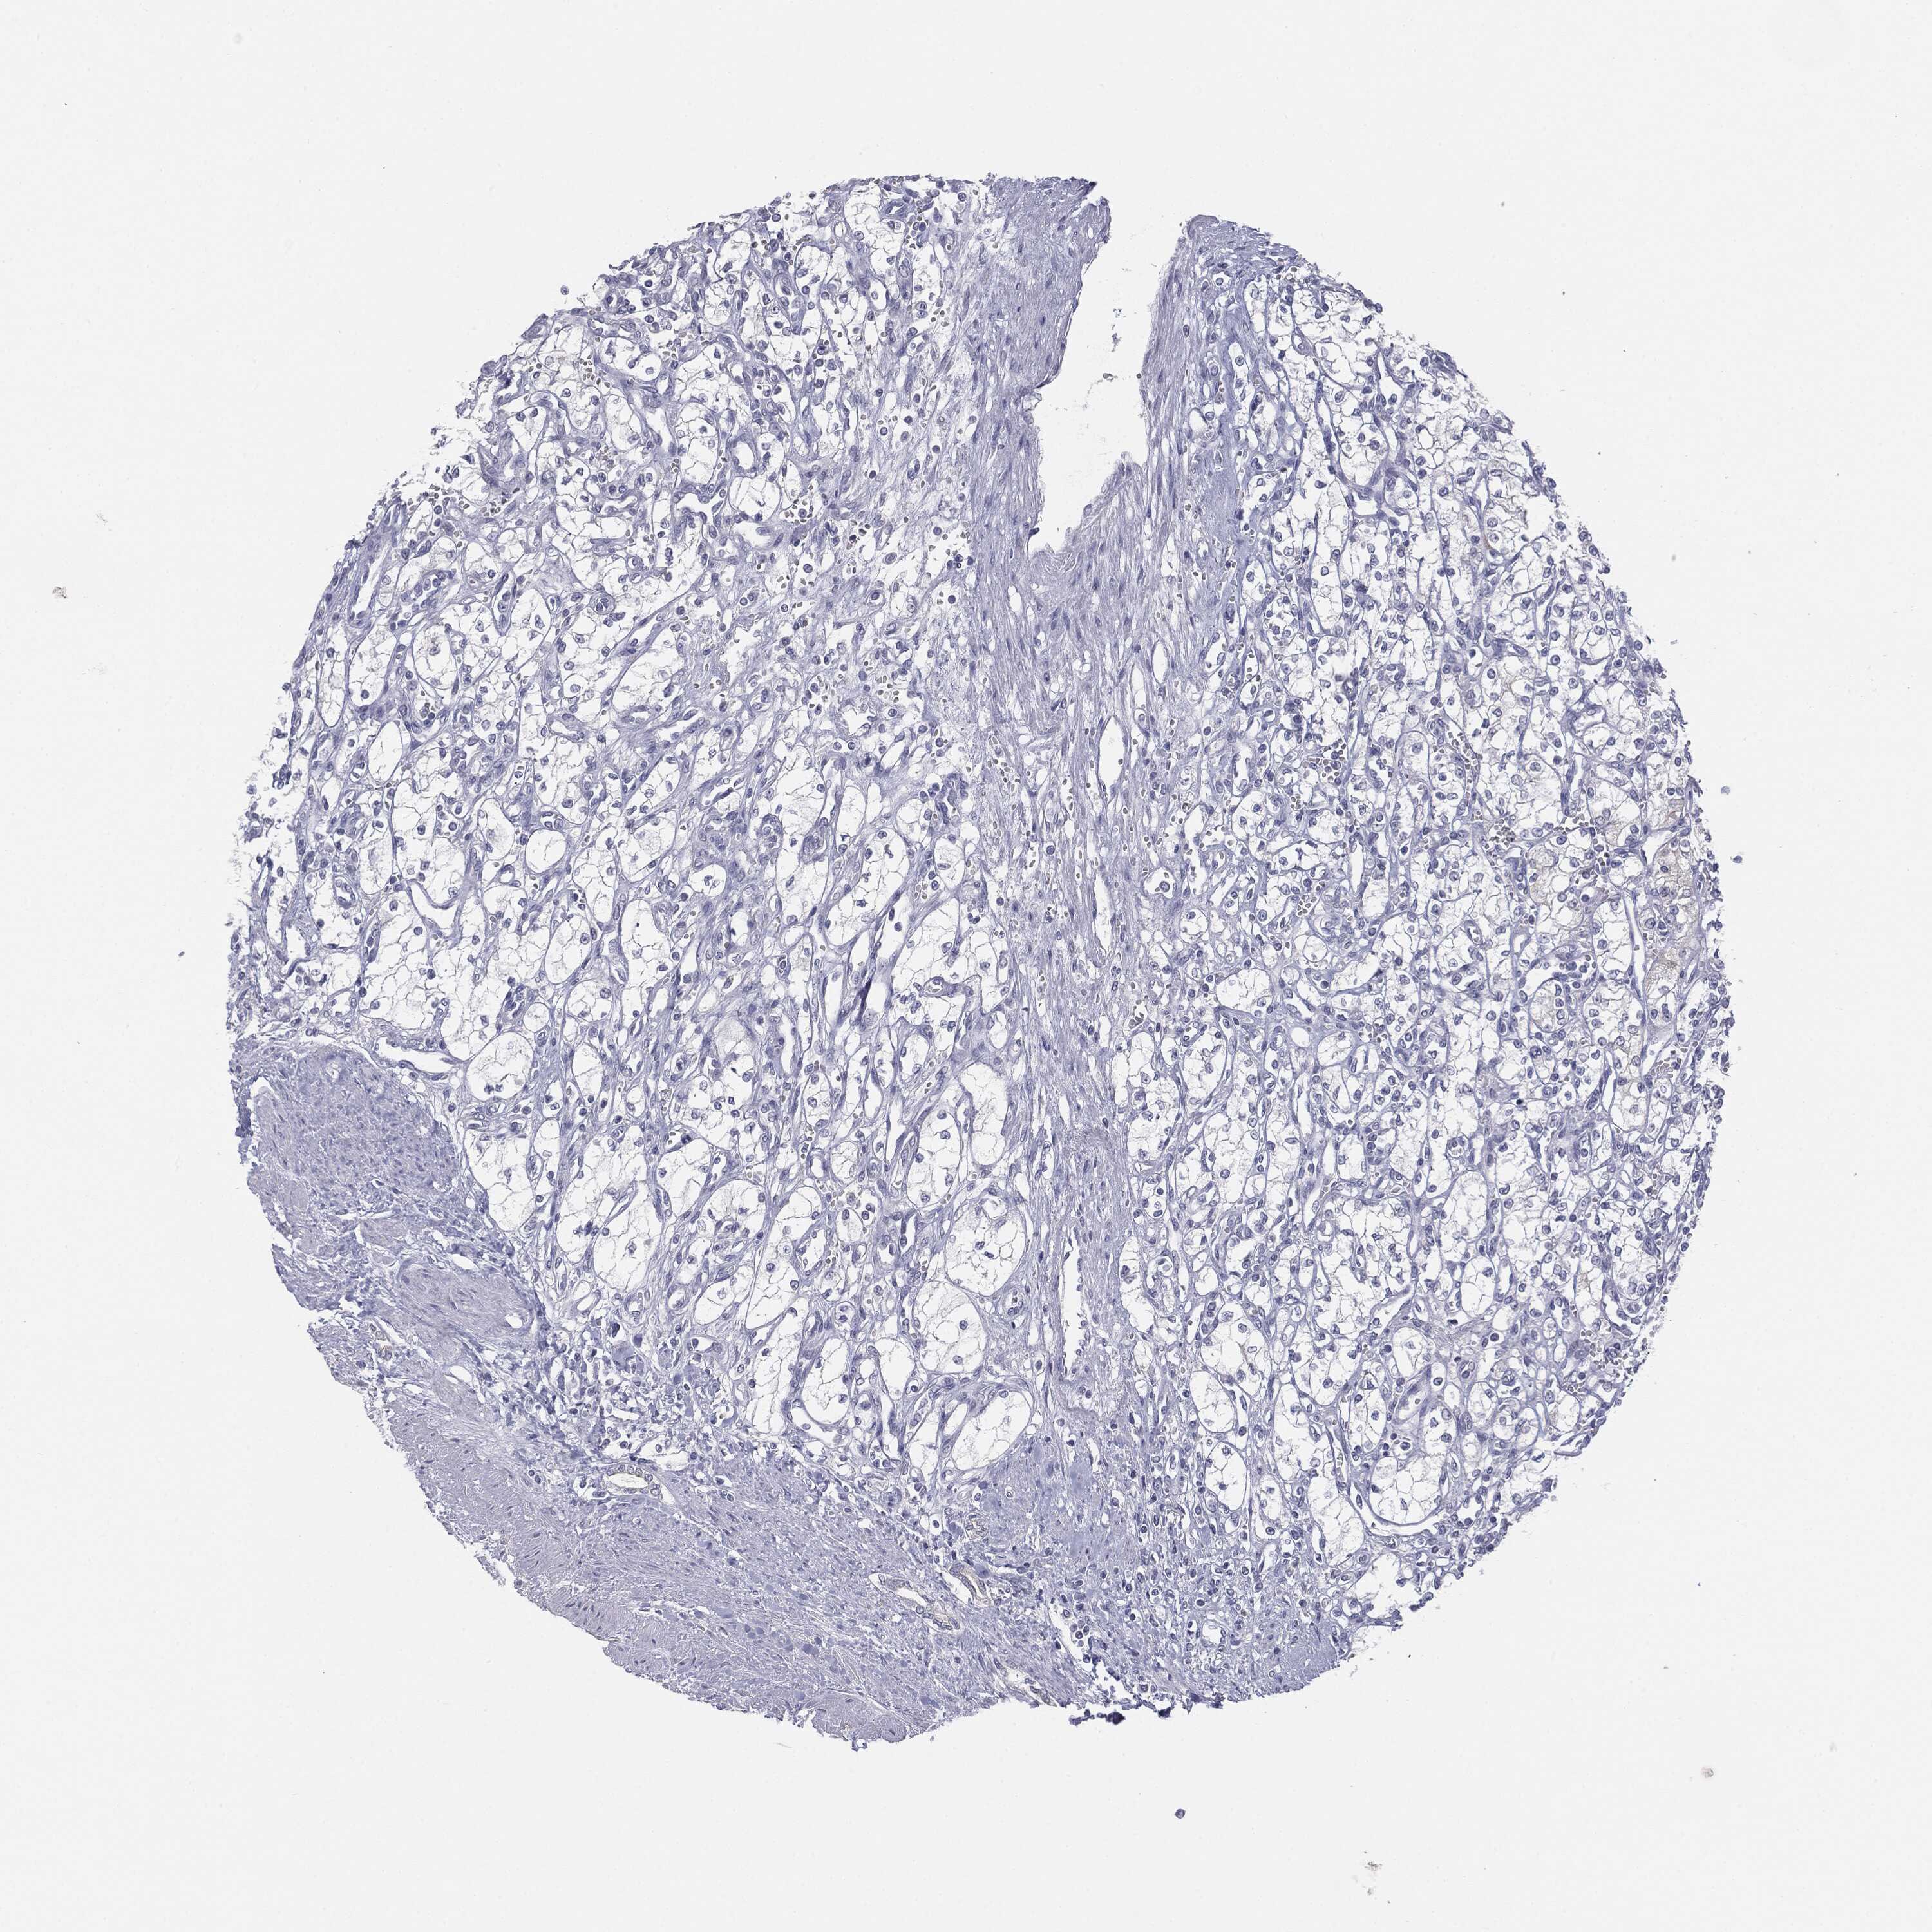

KIDNEY RENAL CLEAR CELL CARCINOMA (VALIDATION) - Interactive survival scatter ploti

The Survival Scatter plot shows the clinical status (i.e. dead or alive) for all individuals in the patient cohort, based on the same data that underlies the corresponding Kaplan-Meier plots. Patients that are alive at last time for follow-up are shown in blue and patients who have died during the study are shown in red.

The x-axis shows the expression levels (FPKM) of the investigated gene in the tumor tissue at the time of diagnosis. The y-axis shows the follow-up time after diagnosis (years). Both axes are complimented with kernel density curves demonstrating the data density over the axes. The top density plot shows the expression levels (FPKM) distribution among dead (red) and alive patients (blue). The right density plot shows the data density of the survived years of dead patients with high and low expression levels respectively, stratified using the cutoff indicated by the vertical dashed line through the Survival Scatter plot. This cutoff is automatically defined based on the FPKM cutoff that minimizes the p-score. The cutoff can be changed by dragging the vertical line or by entering a cutoff value in the square labeled "Current cut-off".

Under the Survival Scatter plot the p-score landscape (black curve; left axis) is shown together with dead median separation (red curve; right axis). Dead median separation is the difference in median mRNA expression between patients who have died with high and low expression, respectively. It is calculated as follows: median FPKM expression of dead patients with high expression - median FPKM expression of dead patients with low expression. This is intended to aid the user in visually exploring custom cutoffs and the associated p-scores and dead median separation.

Individual patient data is displayed and can be filtered by clicking on one or more of the category buttons on the top of the page. Categories describing expression level and patient information include: high, low, alive, dead, female, male and tumor stages. The scale of the x-axis can be toggled between linear and log-scale by clicking on the "x log" button. Mouse-over function shows TCGA ID, patient information and mRNA expression (FPKM) for each patient.

& Survival analysisi

Kaplan-Meier plots summarize results from analysis of correlation between mRNA expression level and patient survival. Patients were divided based on level of expression into one of the two groups "low" (under cut off) or "high" (over cut off). X-axis shows time for survival (years) and y-axis shows the probability of survival, where 1.0 corresponds to 100 percent.

MUC1 is not prognostic in Kidney Renal Clear Cell Carcinoma (validation)

: 24.39

Average pTPM 95.3

Number of samples 100